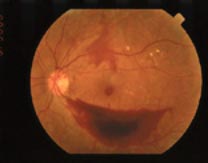

Your eye doctor will examine your eyes and should

use drops to dilate or open the pupils. The doctor will be able to examine the

retina in detail. A photo of a normal retina is seen below.